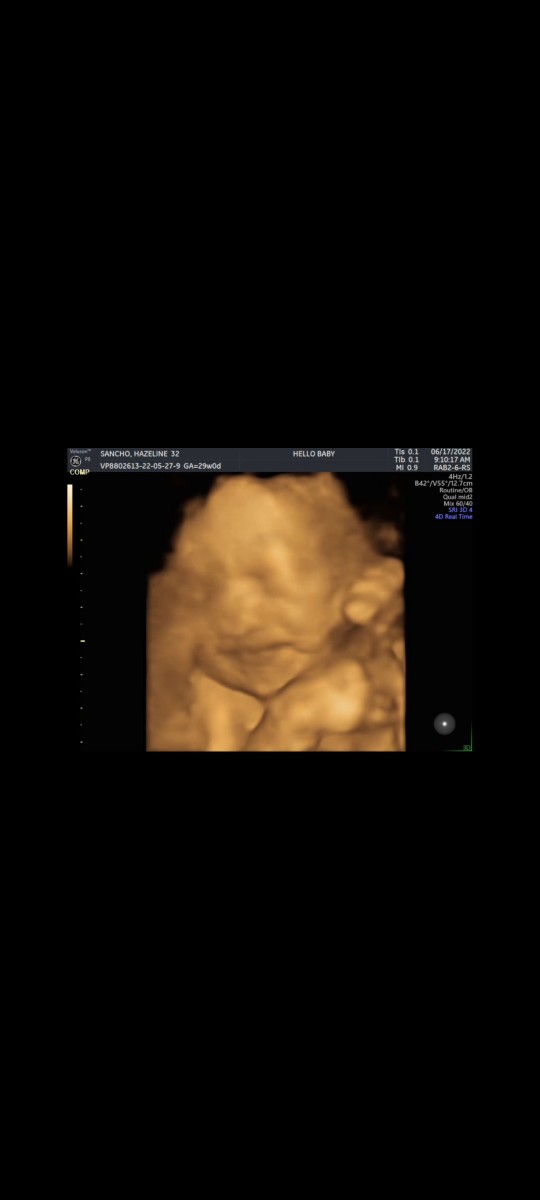

Pregnant 12weeks and 2 days

Preggers